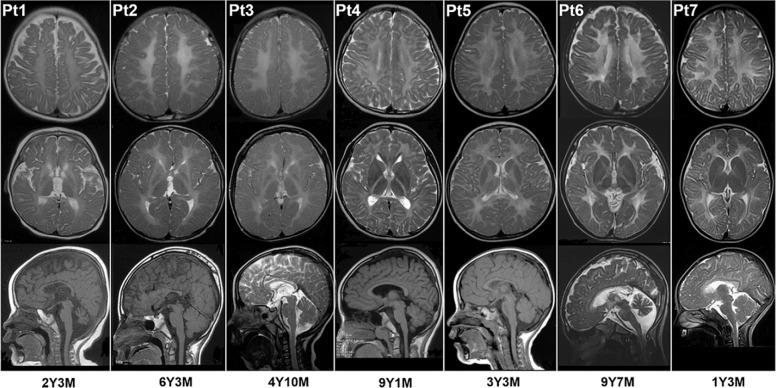

Hypomyelinating leukodystrophies (HLDs) are a rare group of disorders characterized by myelin deficit of the brain-based on MRI. Here, we studied 20 patients with unexplained HLD to uncover their genetic etiology through whole-exome sequencing (WES). Trio-based WES was performed for 20 unresolved HLDs families after genetic tests for the PLP1 duplication and a panel of 115 known leukodystrophy-related genes. Variants in both known genes that related to HLDs and promising candidate genes were analyzed. Minigene splicing assay was conducted to confirm the effect of splice region variant. All 20 patients were diagnosed with HLDs clinically based on myelin deficit on MRI and impaired motor ability. Through WES, in 11 of 20 trios, 15 causative variants were detected in seven genes TUBB4A, POLR1C, POLR3A, SOX10, TMEM106B, DEGS1, and TMEM63A. The last three genes have just been discovered. Of 15 variants, six were novel. Using minigene splicing assay, splice variant POLR3A c.1770 + 5 G > C was proved to disrupt the normal splicing of intron 13 and led to a premature stop codon at position 618 (p.(P591Vfs*28)). Our analysis determined the molecular diagnosis of 11 HLDs patients. It emphasizes the heterogenicity of HLDs, the diagnostic power of trio-based WES for HLDs. Comprehensive analysis including a focus on candidate genes helps to discover novel disease-causing genes, determine the diagnosis for the first time, and improve the yield of WES. Moreover, novel mutations identified in TUBB4A, POLR3A, and POLR1C expand the mutation spectrum of these genes.

Hypomyelinating 脑白质营养不良(HLD)是一组罕见的疾病,其特征在于基于 MRI 的脑髓鞘缺陷。在这里,我们通过全外显子组测序(WES)研究了 20 名原因不明的 HLD 患者,以揭示其遗传病因。在对 PLP1 重复和 115 个已知的白质营养不良相关基因进行基因测试后,对 20 个未解决的 HLD 家系进行了基于 trio 的 WES。分析了与 HLD 相关的已知基因和有前途的候选基因中的变异。进行了 minigene 剪接分析,以确认剪接区域变异的影响。所有 20 名患者均根据 MRI 上的髓鞘缺陷和运动能力受损的临床诊断为 HLD。通过 WES,在 20 个三家中的 11 个中,在 7 个基因 TUBB4A、POLR1C、POLR3A、SOX10、TMEM106B、DEGS1 和 TMEM63A 中检测到 15 个致病变异。后三个基因是刚刚发现的。在 15 个变异中,有 6 个是新的。使用 minigene 剪接分析,证明 POLR3A c.1770+5G>C 剪接变体破坏了内含子 13 的正常剪接,并导致位置 618 处的过早终止密码子(p.(P591Vfs*28))。我们的分析确定了 11 名 HLD 患者的分子诊断。它强调了 HLD 的异质性,基于 trio 的 WES 对 HLD 的诊断能力。包括关注候选基因的综合分析有助于发现新的致病基因,首次确定诊断,并提高 WES 的产量。此外,在 TUBB4A、POLR3A 和 POLR1C 中鉴定的新突变扩展了这些基因的突变谱。